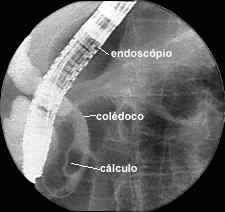

Figuras 5 y 6: Imágenes CPRE.

CPRE de un conducto biliar y pancreático anormales; se muestran cálculos de diferentes tamaños en la vesícula biliar y el conducto cístico.